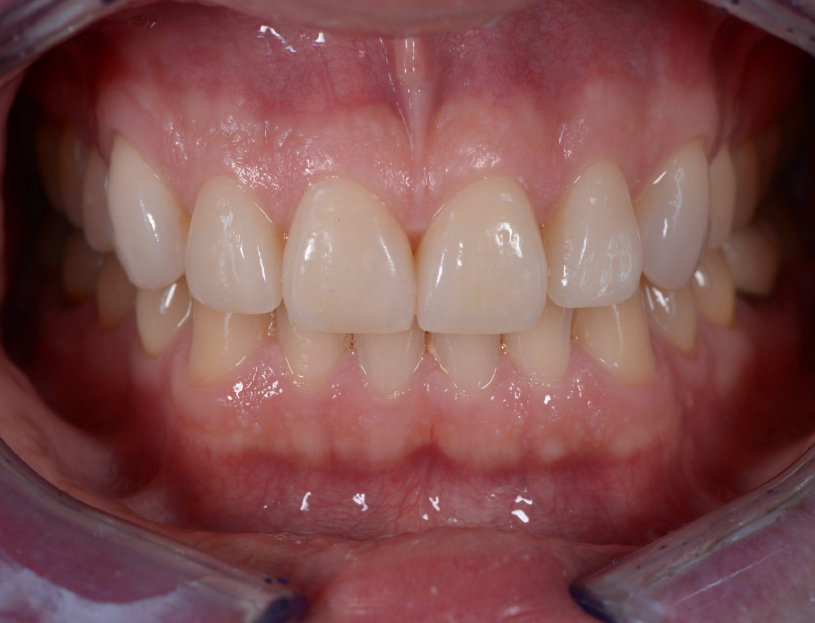

Teeth close-up of upper and lower jaw showing the new upper jaw with attached veneers

Final result two weeks after veneer cementation with 3M™ RelyX™ Veneer Cement , translucent shade.